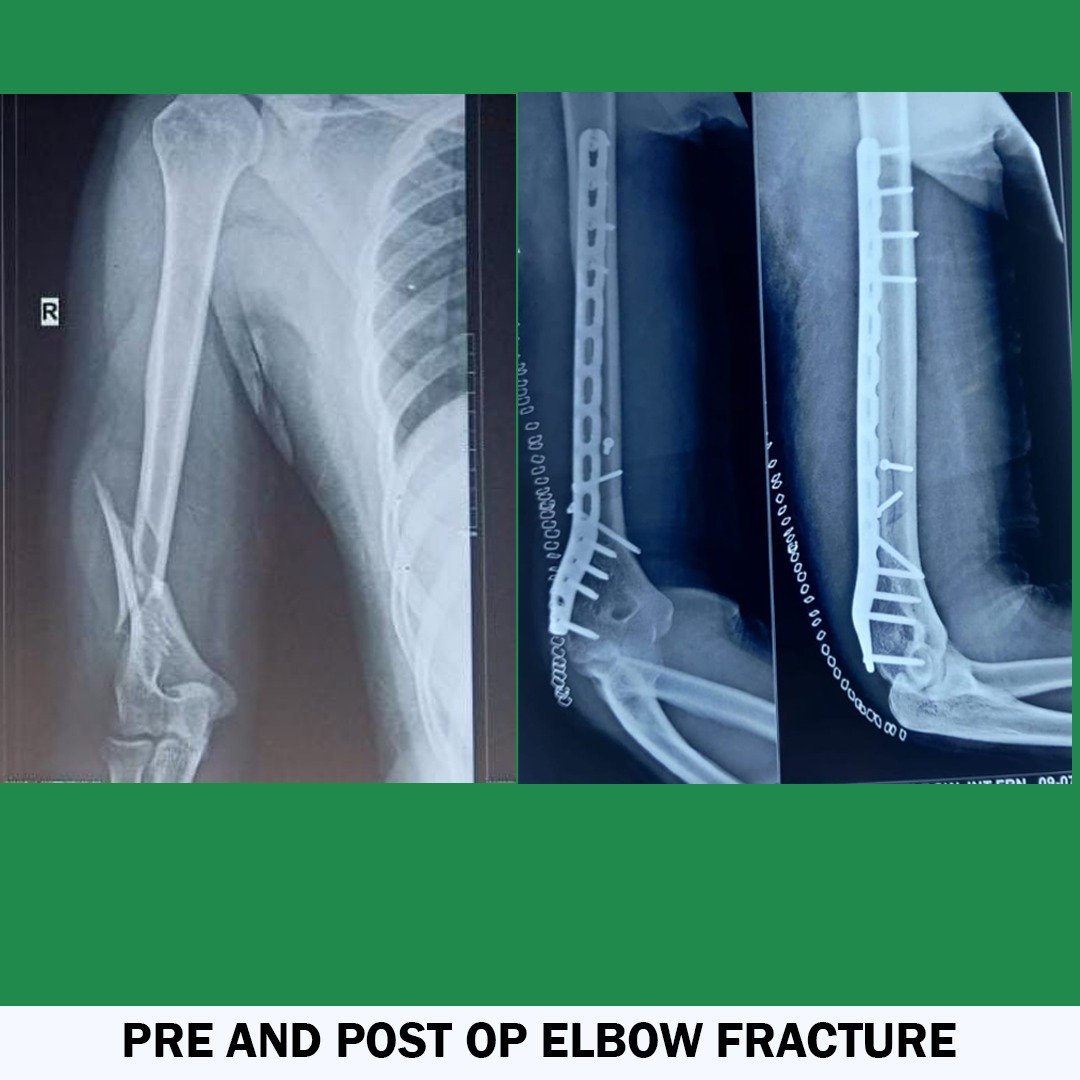

• Orthopedic Trauma Specialist

Dr Ashok K. Sharma is a fully qualified, highly trained, and well-experienced orthopaedic surgeon in India. His Specialization is knee, hip, and shoulder replacement. He is providing the services for more than 13 years. He has performed numerous complicated Joint Replacement and Trauma Surgeries and holds the position of leading Joint Replacement and Arthroscopic surgeon in India. He has done a fellowship in Advance Knee Replacement and Arthroscopic Surgery. Dr. Sharma provides the best consultation on bone-related issues and delivers the best Surgical Outcomes. He is currently associated with Eternal Hospital and Apex Hospital Jaipur, India.